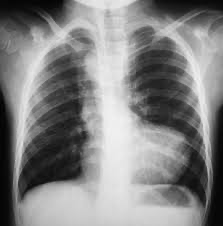

CXR: 장화 모양 심장(Boot-shaped heart)

CXR: 심장의 Egg on side 소견

CXR: 매우 큰 심장 (box shaped heart)